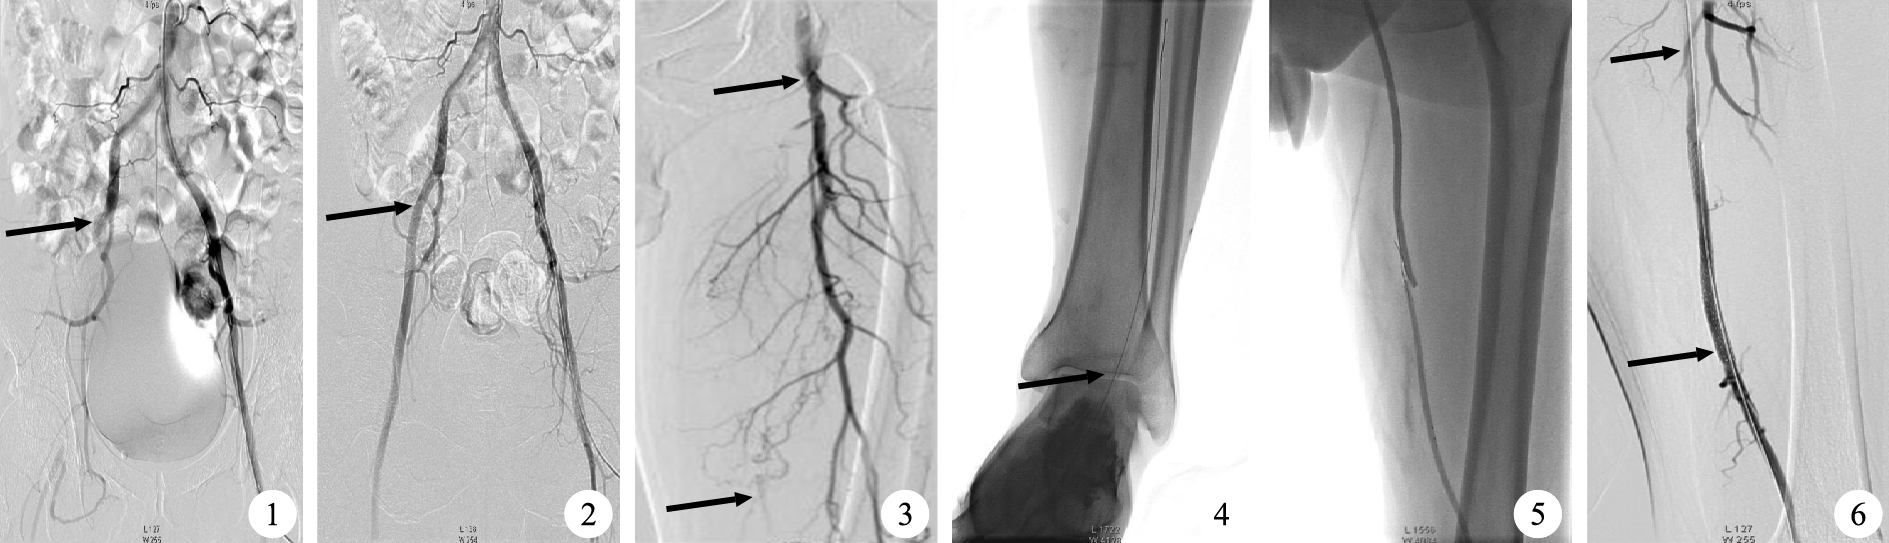

①聯合組。溶栓導管置入閉塞段內的16例患者經置管溶栓后,僅行球囊擴張,血流即恢復通暢,無需置入支架(圖 1和圖 2)。溶栓導管置入閉塞段近端的17例患者經置管溶栓后,其中6例患者的導絲順行通過閉塞段,并成功進入遠端流出道,其中僅行球囊擴張者4例,行球囊擴張和金屬裸支架置入者2例,DSA顯示血流均恢復通暢。其余11例患者的導絲仍不能順行通過閉塞段,術中在血管B超引導下逆行穿刺足背動脈4例,脛后動脈3例,小腿中段脛前動脈1例,大腿下段股淺動脈3例;再行雙球囊擴張(部分置入支架),其中置入金屬裸支架4例(圖 3~6),DSA顯示10例患者的血流恢復通暢。②介入組。31例患者中有16例患者的導絲能順行通過閉塞段,進而均行球囊擴張,其中置入金屬裸支架者8例,置入覆膜支架者2例,DSA顯示血流均恢復通暢。其余15例患者的導絲不能順行通過閉塞段,則術中在血管B超引導下逆行穿刺足背動脈6例,脛后動脈3例,小腿中段脛前動脈1例,大腿下段股淺動脈5例,進而均行雙球囊擴張(部分置入支架),其中置入金屬裸支架10例,DSA顯示10例患者的血流恢復通暢。聯合組患者的血管開通率為97.0%(32/33),較介入組的83.9%(26/31)高(χ2=8.9,P<0.05);聯合組患者的球囊擴張率為100%(33/33),與介入組的100%(31/31)相比無差異;聯合組患者的支架置入率為18.2%(6/33),較介入組的64.5%(20/31)低(χ2=2.4,P<0.05);聯合組患者的手術時間為(2.0±0.5)h,較介入組的(4.0±1.1)h縮短(t=22.4,P<0.05)。